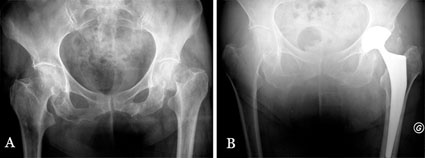

Die in dieser Studie implantierte tripolare Pfanne besteht aus einer M30NW-Stahlaußenschale mit hochpolierter Innenseite für das darin gleitende bipolare UHMW PE-Inlay vom Typ SATURNE der Firma Amplitude (Abb. 4). Der Femurkopf wird mittels Verpressung intraoperativ im Inlay verankert und gemeinsam mit diesem auf das Femurschaftimplantat impaktiert. Die Pfannenaußenschale wurde in 165 Hüften zementfrei (mit Titanplasma- und Hydroxylapatit-Beschichtung) implantiert und in 2 Fällen unter Verwendung einer Pfannendachverstärkung zementiert implantiert. In 157 Hüften (94%) wurde ein Femurschaftimplantat mit einheitlichem Design verwendet. Die HA-beschichtete Ausführung, Typ INTEGRALE der Firma Amplitude, wurde in 147 Fällen zementfrei implantiert (Abb. 5 und 6), in 10 Fällen wurde die zementierte Ausführung, Typ GENERIC, verwendet. In den übrigen 10 Fällen war eine endoprothetische Rekonstruktion des proximalen Femurs mit einem Rekonstruktionsschaft erforderlich.